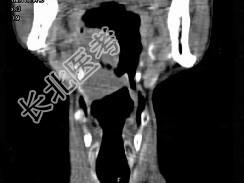

- 单项选择题男,74岁, 咽喉部不适一年余,近两三个月咽喉疼痛, 吞咽困难,CT如图所示, 最可能诊断是  (    )

- A、喉癌

- B、会厌癌

- C、声带癌

- D、声门下区癌

- E、跨声门型癌